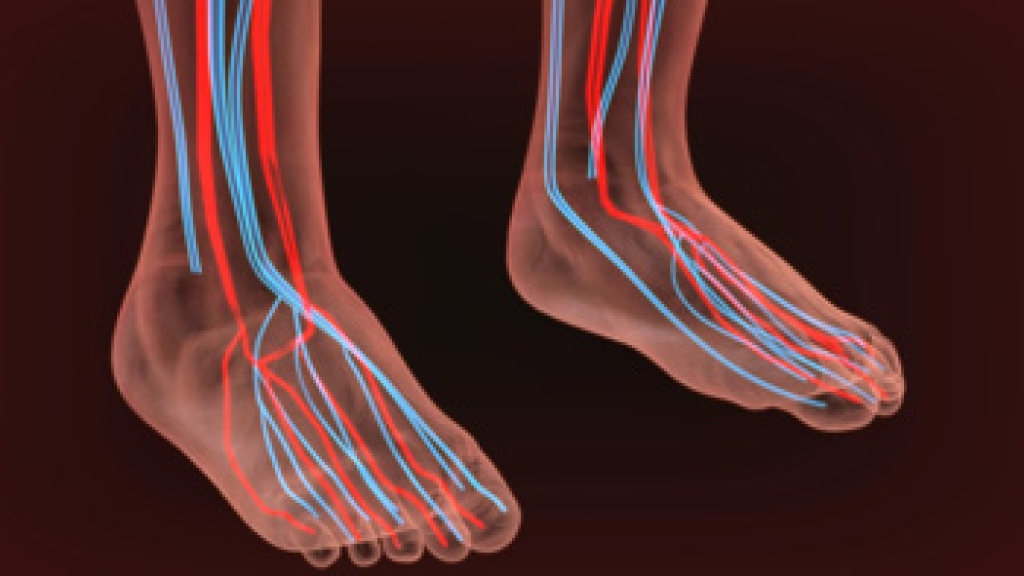

Peripheral artery disease

Peripheral artery disease